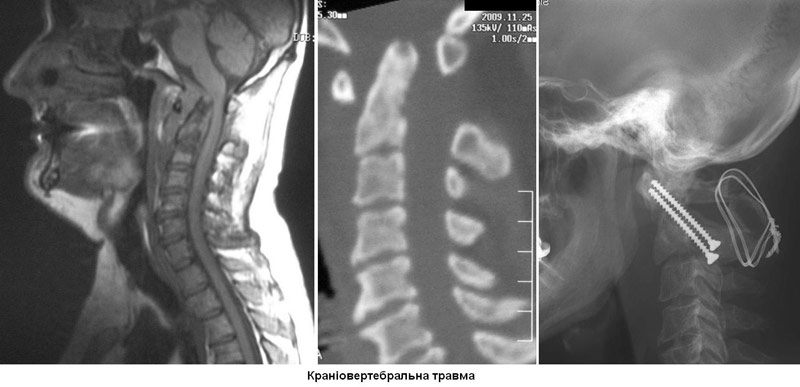

- Рентгенографію. Медпрацівники зазвичай проводять рентгенографію всім травмованим, у кого є підозра на пошкодження спинного мозку. Рентген може виявити проблеми з хребцями, пухлини, переломи або дегенеративні зміни в хребті.

- Комп'ютерну томографію (КТ). КТ може надати краще зображення патології, видимої на рентгенівських знімках. Цей вид обстеження використовує комп'ютер, щоб відтворити серію зображень поперечного перерізу, які можуть виявити проблеми, пов'язані з кістками, дисками і інші.

- Магнітно-резонансна томографія (МРТ). МРТ використовує магнітну силу і радіохвилі, щоб відтворити зображення, отримані через комп'ютер. Це допомагає в ситуаціях, коли необхідно розглянути спинний мозок і виявити грижу міжхребцевого диску, згустки крові і інші утворення, які можуть здавлювати спинний мозок. Але МРТ не можна проводити пацієнтам з серцевими водіями ритму або постраждалих, яким необхідна апаратура, що підтримує життєдіяльність організму чи пристосування для витягування шийного відділу хребта.

Мета операції - стабілізація хребта металевими конструкціями (імплантантами). Наша клініка була першою в СНД, яка застосувала сучасні конструкції при переломах хребта. Нині ми використовуємо імпортні конструкції типу CD Horison Legacy (США), Atlantis (США), Sextant (США), Socore (Франція). Операції вимагають складної рентгенівської техніки та спеціального інструментарію. При неускладнених переломах хребта хворі можуть ходити після таких операцій уже на другий - третій день. Також в Міжнародному центрі нейрохіургіі вперше в Україні впроваджено метод мініінвазивних операцій при переломах хребта.

Краніовертебральна травмаТравми шийного відділу хребтаТравми грудного відділу хребтаТравми поперекового відділу |